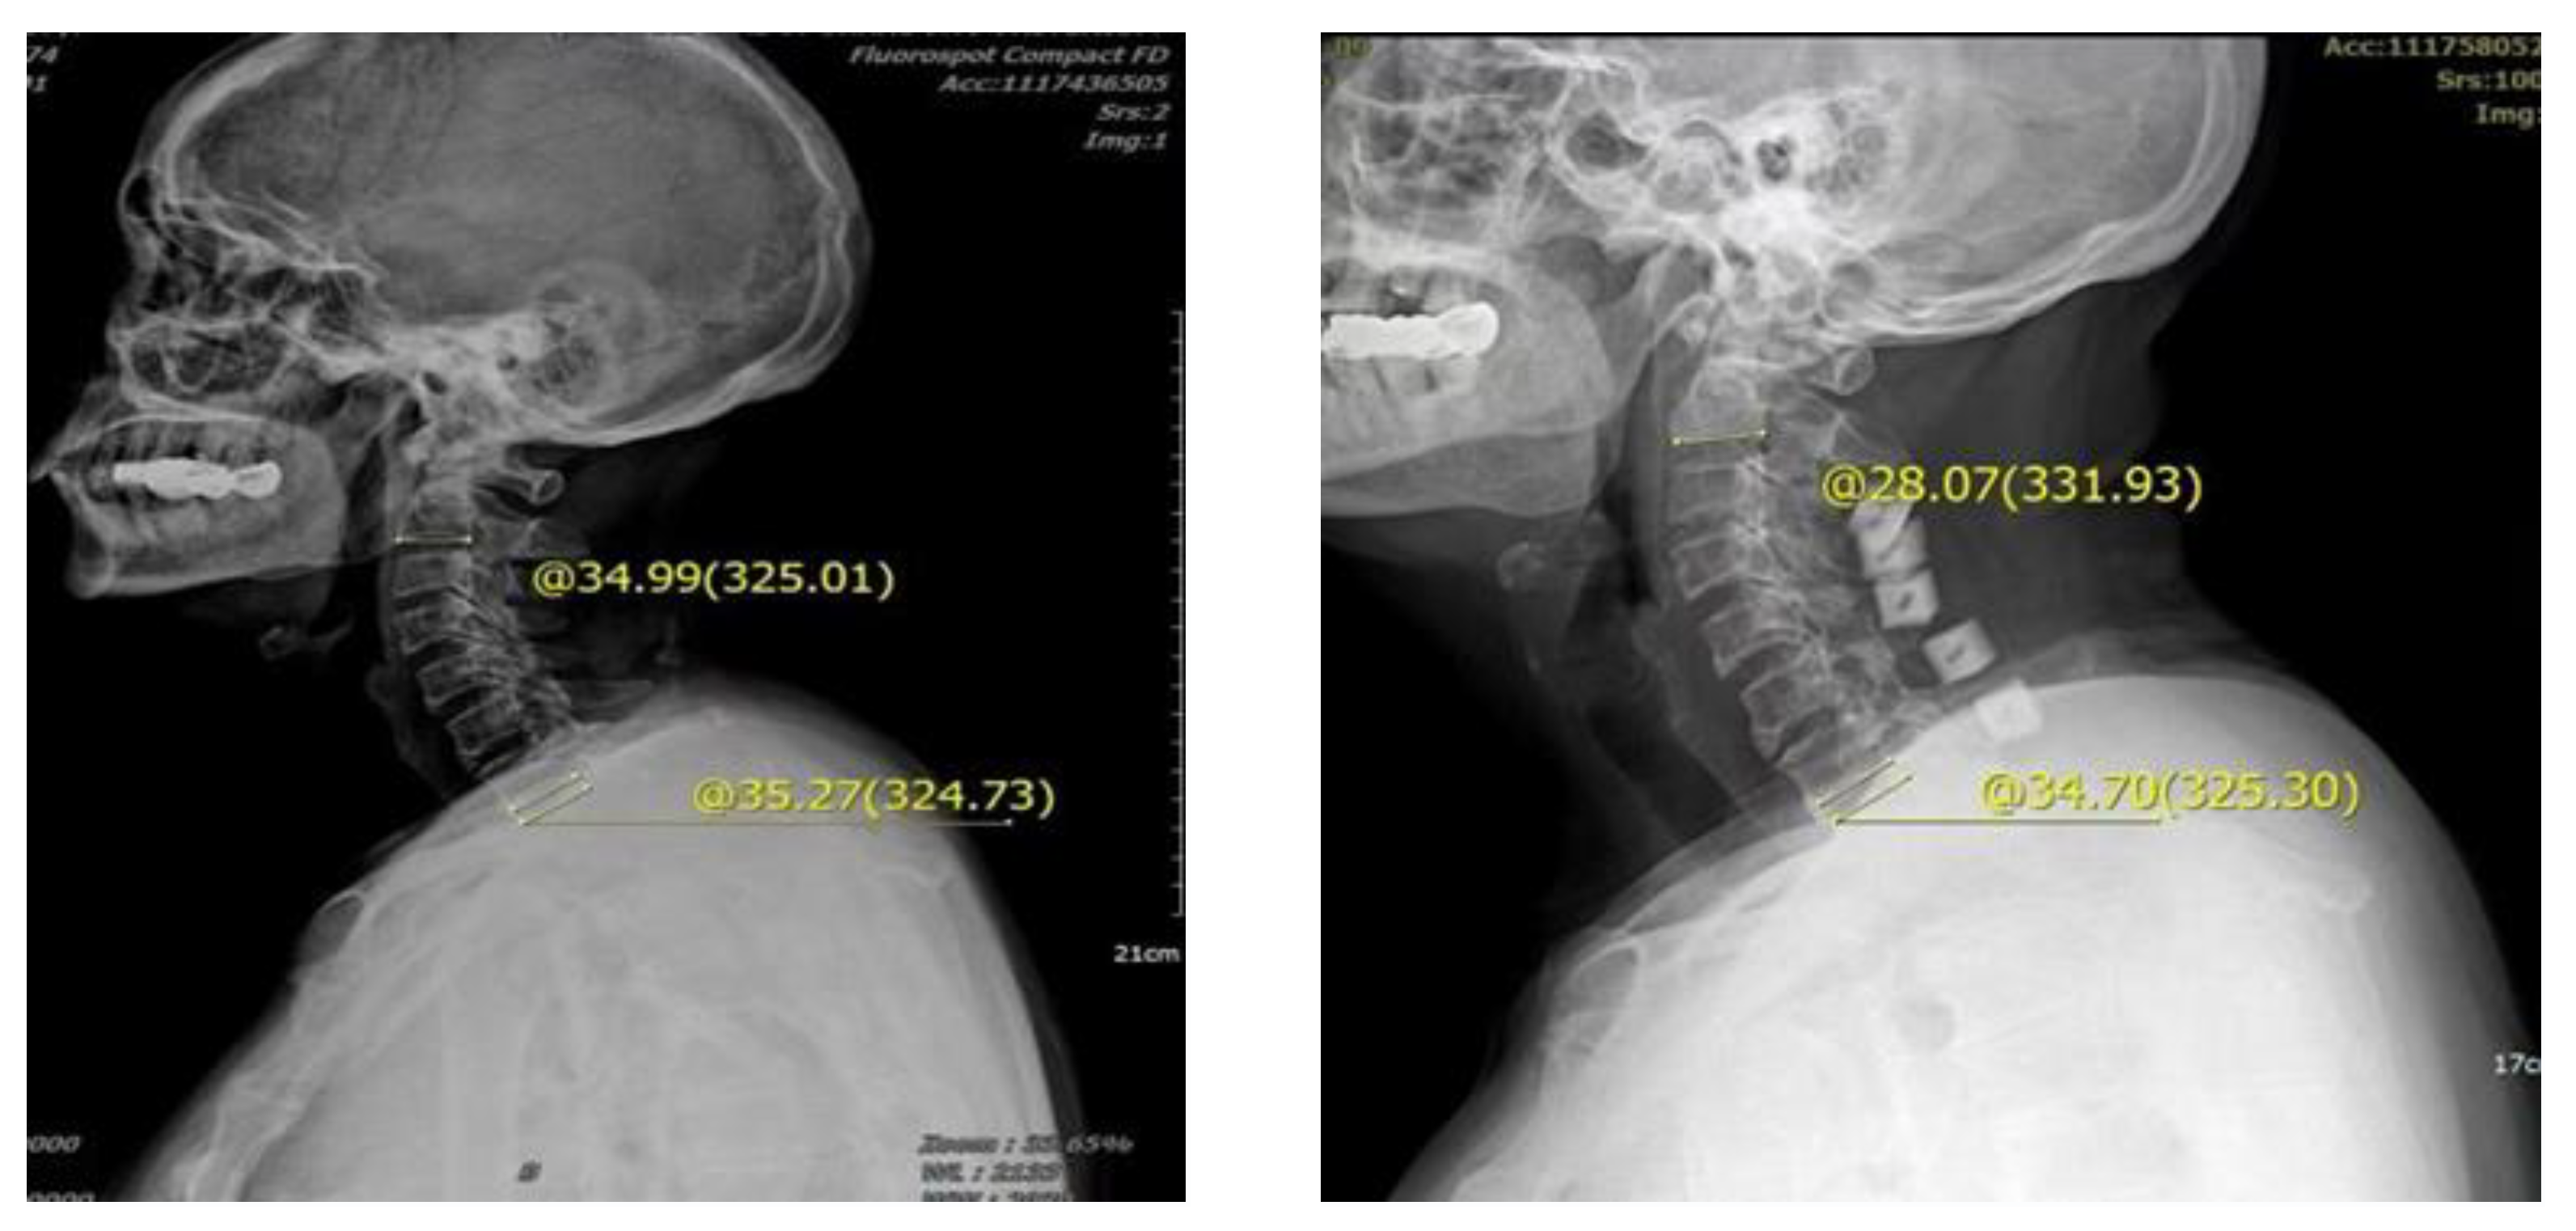

2.3. Measurement Standard